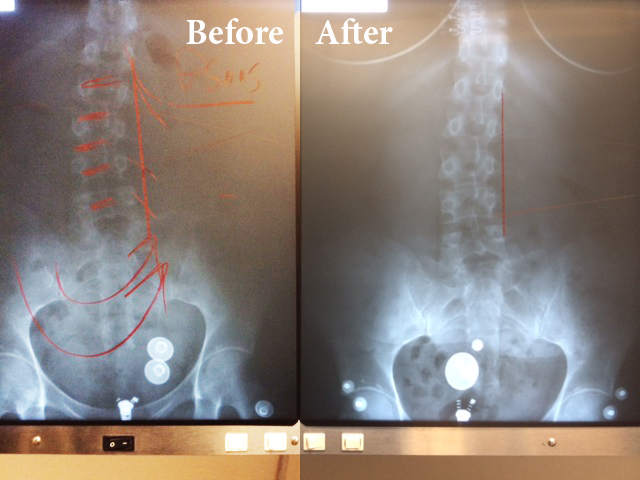

This is a 41 YOA female. The radiography on the left is the beginning of treatment. The radiography on the right is only after 8 treatments on the ATM2 Pro.

41 YOA female after 8 ATM2 teatments